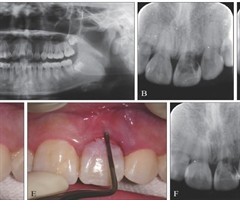

牙体显微分层修补术治疗上颌中切牙牙颈部外吸收1例

[摘要]牙吸收是在破牙细胞持续作用下发生的牙齿硬组织破坏。牙颈部外吸收是由于牙周膜或上皮下牙骨质破坏和(或)缺陷导致的牙齿颈部吸收。本文报道1例上颌中切牙外伤及正畸后牙颈部外吸收,术前通过锥形束CT充分了解患牙吸收部位和形态,术中利用显微技...